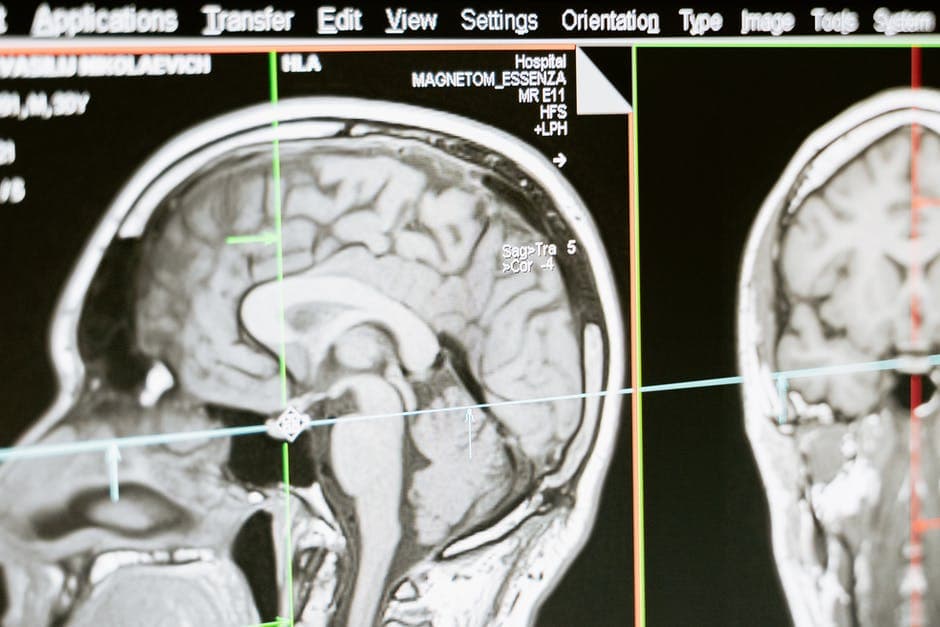

What Is an MRI?

An MRI (short for magnetic resource imaging) is a test that takes a picture of the inside of your body. It does this by making use of radio waves and magnets. You can get a general MRI of your body, or have it more localized to specific parts.

MRIs are more useful than X-rays, which just look at bones. By getting a good view of soft tissue and nerves, an MRI can help diagnose an injury or a disease. They're good for diagnosing cancer, strokes, eye problems, and heart disease.

MRIs are extremely important when it comes to any condition that deals with internal organs. MRIs are able to get three-dimensional images, so you're not going to want to pass them over for more conventional forms of imaging. They're also extremely important for anything involving the nerves, the brain, and situations involving tumours.